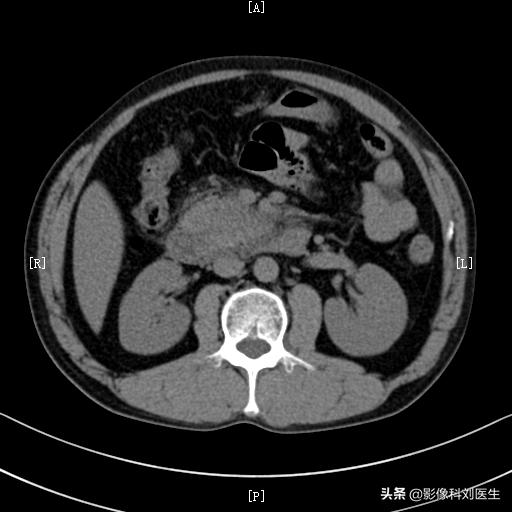

3、腹部CT检查。是诊断胰腺炎最重要的影像学检查。它可以观察胰腺肿大的情况,胰腺周围的渗出情况,通过三期增强扫描,可以判断胰腺组织内是否有坏死,周围是否有假性囊肿形成等。通过CT检查,可以明确急性胰腺炎的分型,了解其并发症情况,对其严重程度进行分级,所以是诊断急性胰腺炎的最佳方法。

急性水肿型胰腺炎:胰腺肿大,边缘毛糙,见多发条索影。

同一病人:胰周脂肪间隙模糊